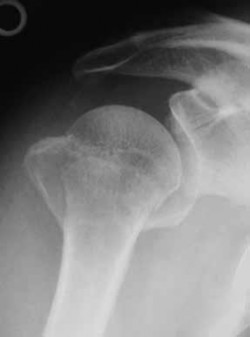

A 65-year-old active female presents to the emergency department after a mechanical fall. She complains of severe right groin pain and inability to bear weight. A representative radiograph of her injury is shown below. Assuming the image demonstrates a displaced (Garden IV) femoral neck fracture, which of the following is the most appropriate surgical intervention to maximize her functional outcome and minimize her lifetime revision rate?

Options:

Correct Answer: Total hip arthroplasty

Explanation:

For active, physiologically young older adults (typically 65-75 years old) with displaced femoral neck fractures, Total Hip Arthroplasty (THA) is the treatment of choice. Multiple randomized controlled trials have demonstrated that THA yields better long-term functional outcomes (e.g., higher Harris Hip Scores) and lower reoperation rates compared to hemiarthroplasty. Hemiarthroplasty (unipolar or bipolar) is generally reserved for lower-demand, older, or cognitively impaired patients. Internal fixation with cannulated screws for a Garden IV fracture in this age group carries an unacceptably high risk of nonunion and avascular necrosis.